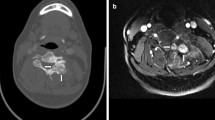

Examples of patterns of bone destruction: A- Geographical type of bone destruction pattern seen in a skull base chordoma centered dorsally in the clivus (arrows). extending into the apex os petrosum bilaterally. B- Example of permeated/moth-eaten type of bone destruction pattern seen in sacral chordoma (arrows)

Calcifications

Rings-and-arcs/popcorn-type calcification was seen on CT in 12 out of 78 patients (15.4%) all diagnosed with chondrosarcoma (Fig. 4A). Amorphous-type calcification (due to pre-existing bone) was seen in 28 patients out of 78 patients (35.9%), all diagnosed with chordoma—12 located in the skull base, 2 in the mobile spine and 14 in the sacrum (Fig. 4B). Dense sclerotic-type calcification was seen in only 3 patients (3.8%), all diagnosed with osteosarcoma (Fig. 4C). In 35 patients (44.9%) no calcification was present. (Table 2).

Examples of different calcification types: A- Axial view CT scan of a skull base chondrosarcoma showing rings-and-arcs/popcorn-like calcification (arrows). B- Axial view CT scan of sacral chordoma showing linear bone remnants (amorphous-like calcification) consistent with pre-existing bone (arrows). C- Axial view CT scan of sacral osteosarcoma presenting with dense sclerotic-like (osteoid) calcification (arrow)